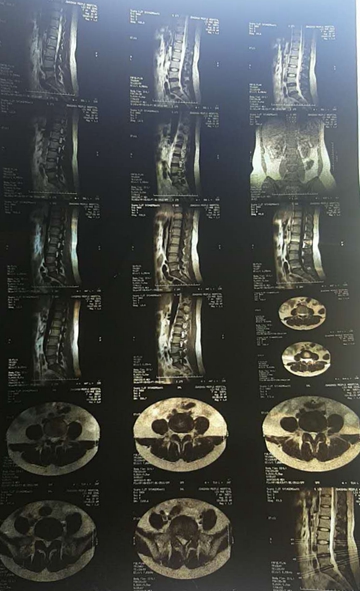

核磁轴位

核磁矢状位

2007年,刘女士,43岁,L5-S1椎间盘脱出0.8cm,胶州市人民医院外聘专家要求手术。不能行走,夜间痛性,主要表现为腿后侧。

2011年,小张(20岁),L4-5椎间盘脱出,高密人民医院、青岛山大医院要求手术。右腿外侧疼痛,迈不开步子,直腿抬高不过20°。